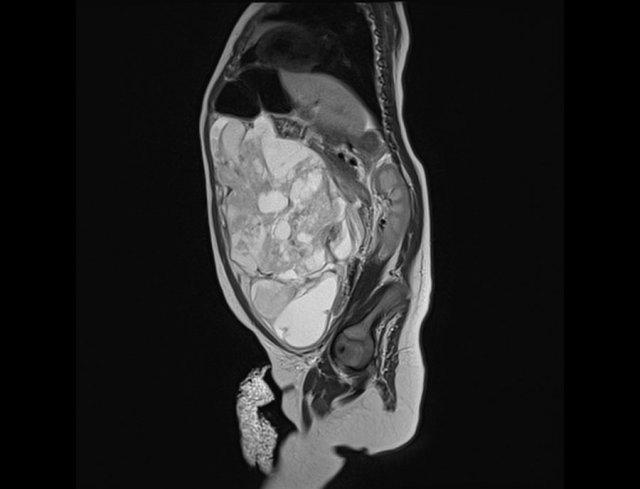

Hình MRI cắt dọc cạnh đường giữa cho thấy một khối dạng nang trước xương cùng.

Bé gái sơ sinh với u quái vùng cùng cụt có thành phần đặc và dạng nang cả bên ngoài lẫn bên trong, kèm theo sự xâm lấn lớn vào ống sống.